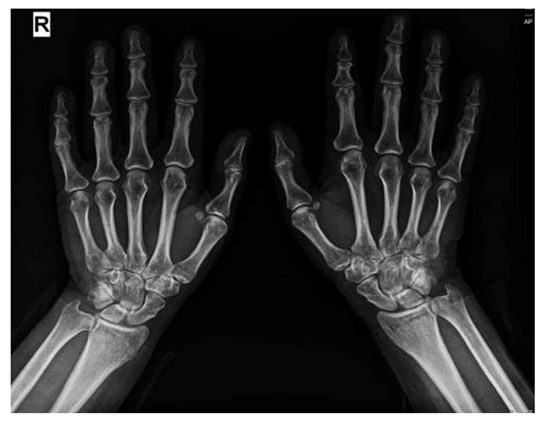

2. Case Presentation